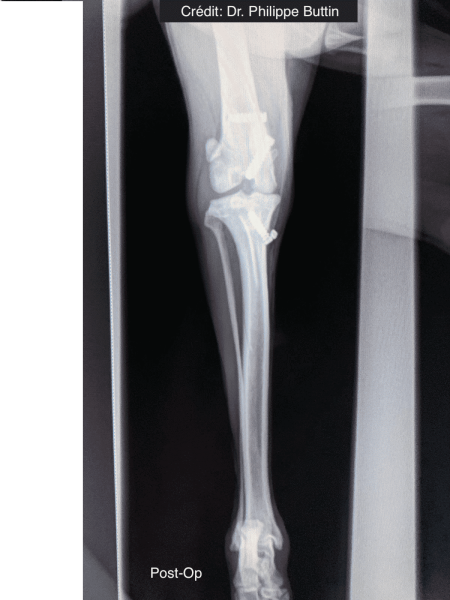

Radiologické snímky